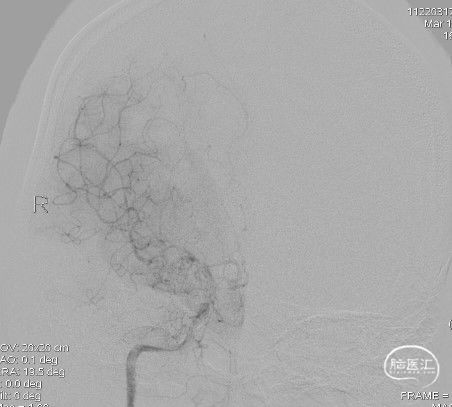

右侧颈内动脉正位:

造影:右侧颈内动脉末段变细,右侧大脑中动脉M1段分叉前重度狭窄,豆纹动脉增多,右侧大脑前动脉向大脑中动脉分布区代偿供血:

三维重建显示右侧大脑中动脉分叉前部重度狭窄,狭窄段直径0.4mm,狭窄程度约84%: